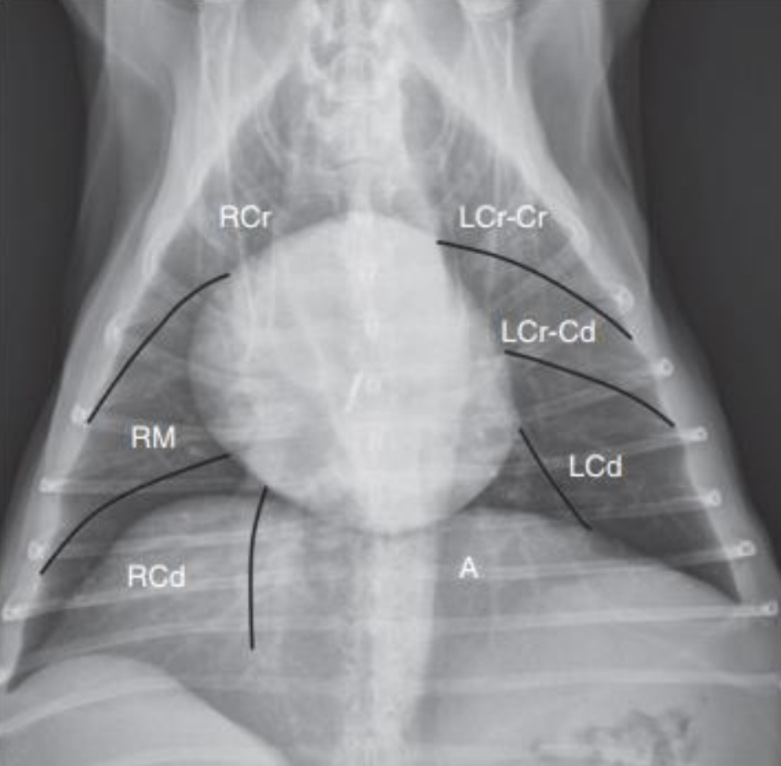

- ์ฐ 4์ฝ, ์ข 2์ฝ์ผ๋ก ์ด 6์ฝ์ด๋ค.

- ์ธ์ธก์์ ๊ฒน์ณ ๋ณด์ฌ ์ ํธ๋์ง ์๊ณ , DV๋ VD - ํนํ VD๊ฐ ์ ํธ๋๋ค.

- DV : ์์ ๋ ์์ธ, ๊ธฐํ ์ดฌ์

- VD : ํ์ ์ดฌ์

- ํธํก๊ณค๋, ๊ธฐํ ์์ฌ๋ ๋๋ DV ์ดฌ์ (์์ธ ๋ค์ง์ผ๋ฉด ํ๋ค์ดํจ)